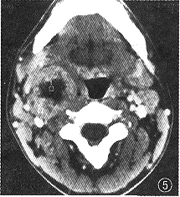

1.肿瘤CT增强影像表现特殊,可分为以下几类:(1)低密度区中伴团状高密度改变24个(图1),病理改变为在比较广泛分布的疏细胞区(Antoni B区)组织中,有相对集中分布的富细胞区(Antoni A区)(图2)。(2)弥漫点状改变20个,点状大小从1~4 mm不等,其密度不等。高密度CT值为60~80 HU,低密度为40~45 HU,两者CT值相差约20 HU。其中呈低密度点状4个;高密度点状4个;高、低密度混杂点状12个(图3)。此20个肿瘤中8个伴有1~2个形态不规则的低密度裂隙样变。高低密度混杂点状分布的病理改变为的Antoni A区、Antoni B区相互交错,分布均匀(图4)。低密度点状改变为比较广泛分布的Antoni A区或胶原基础上出现的零星分布的Antoni B区或微囊集中处,Antomi B区或微囊分布较集中时,即表现为低密度裂隙样改变。较广泛分布的Antoni B区伴少量Antoni A区或胶原则呈高密度点状改变。(3)低密度环伴中央弥漫不同密度点状改变5个,其中单纯为低密度点状或单纯为高密度点状各1个。此低密度环在病理上由Antoni B区组成。(4)中央低密度伴有环形改变8个(图5),环壁厚,环表现各异,其中表现为高、低密度混杂点状分布的3个,单纯低密度点状或高密度点状各2个,环与肌肉呈等密度1个。肿瘤中央的低密度区病理上由Antoni B集中区和(或)陈旧性出血区组成。(5)密度均匀的12个肿瘤中,等密度与低密度各5个,囊性变2个。在病理上等密度多由Antoni A区及胶原组成,Antoni B区较少,分散在Antoni A区及胶原间;而低密度肿瘤(图6)为均匀一致的Antoni B区及部分陈旧性出血组成,几乎无Antoni A区细胞(图7)。囊性肿瘤巨检时见黄色液体流出,囊壁上仍见典型Antoni A、Antoni B区改变。(6)增强特别明显的肿瘤3个,其中2个为弥漫点状改变(图8),1个为厚环。病理显示此3个肿瘤由丰富的Antoni A区组成,夹杂有微囊,而Antoni B区少见(图9),其中仅2个血供比较丰富。

图1 右颈神经鞘瘤。CT增强扫描,示中央偏内侧为高密度区(箭),周围以低密度区为主

图5 右颈神经鞘瘤增强扫描,示肿瘤呈厚环改变